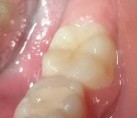

Bệnh nhân: Trần Nguyệt H. 7 tuổi, Răng 46, mã BA 11907/17

Sau sáu tháng. ICDAS: 1; Di: 15 | Sau chín tháng. ICDAS: 0; Di: 13 | Sau 18 tháng. ICDAS 0; Di:7 |